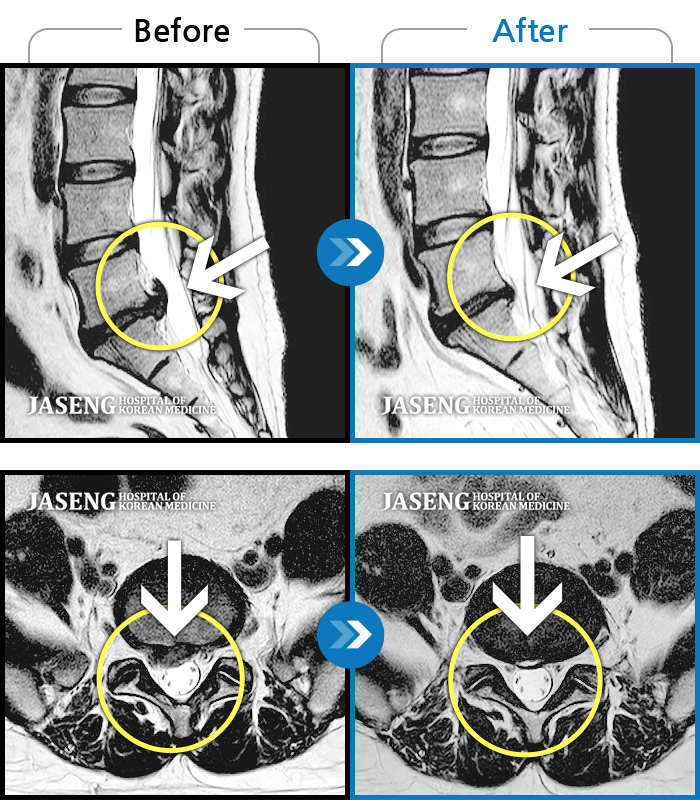

Before

After

환자에게 사전 동의를 받아 동일 조건에서 촬영되었습니다.

개인에 따라 치료 후 부작용이 발생할 수 있으니 의료진과 상담 후 치료를 진행하시기 바랍니다.